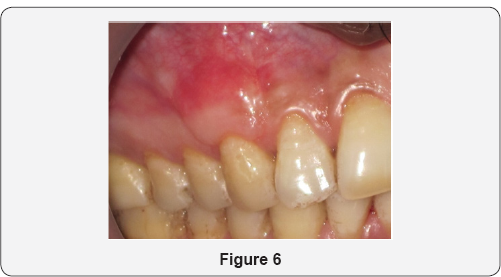

Patient aged 34 years reported to the department of Periodontology with the complaint of long corner tooth with sensitivity. On clinical examination, gingival recession was observed on maxillary right canine (Figure 1). Diagnosis was made as Miller's Class I gingival recession with 13. Coronally advanced flap with alloderm with microsurgical approach was planned. Patient's consent as well as ethical clearance was obtained prior to the surgical intervention. Following administration of local anesthesia, the tooth with the recession was root planed. A split-thickness flap with two vertical releasing incisions with micro scalpels was raised with microelevaters, and the papillae were de-epithelialized (Figure 2). Alloderm was measured, cut and rehydrated before suturing it with chromic gut 5-0 covering the defect as shown in Figure 3. The flap was coronally moved and secured to the de-epthelialized papillae over the alloderm with interrupted sutures (5-0 black braided silk) as shown in Figure 4. Pressure was applied before placing the periodontal dressing on surgical wound. Sutures were removed on 10th day and healing was found to be satisfactory (Figure 5). Healing is generally uneventful in minimally invasive surgery. Patient was evaluated after 3 months; there was 100% coverage of a denuded root with satisfactory gingival thickness and color match with microsurgical reconstruction of lost gingival (Figure 6).